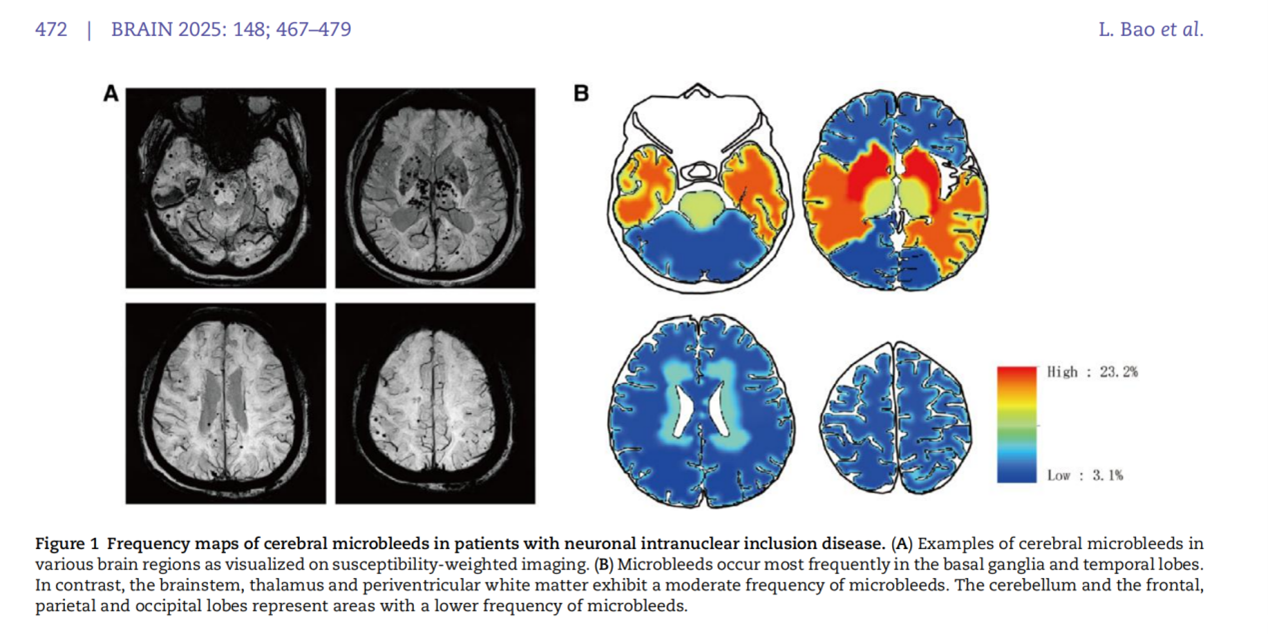

该研究成果显示,NOTCH2NLC 基因 GGC 重复扩增会使其翻译出富含甘氨酸的蛋白质 uN2CpolyG。这种蛋白质不仅会在神经元内聚集形成包涵体,还能沉积在血管壁形成淀粉样物质,导致患者出现进行性认知功能障碍、多发脑微出血、反复皮层下梗死、关键脑区白质病变(外囊、颞极)、脑叶出血等症状。这一发现有助于解释神经元核内包涵体病患者特有的一些临床表现,像卒中样发作、癫痫发作、偏头痛发作、脑炎样发作等,这些症状实际上可能是由脑血管淀粉样变引起的短暂性局灶性神经系统发作(TFNE),即 “淀粉样发作(amyloid spells)”。